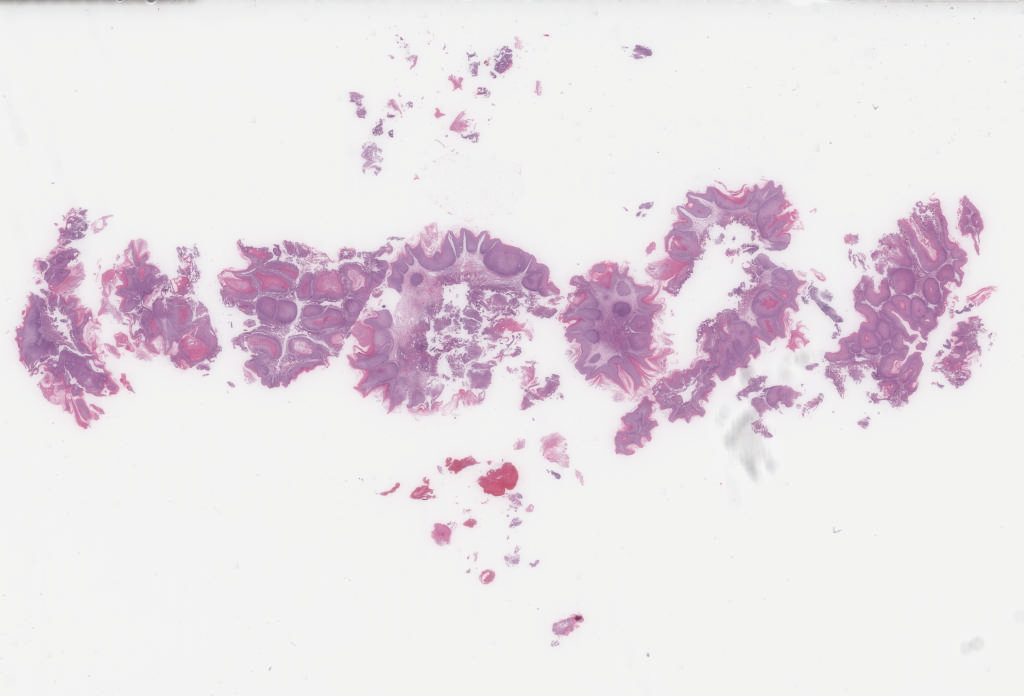

Case2.svs

51791

x

50489

@

40X